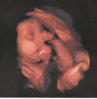

Mama Ninki :)